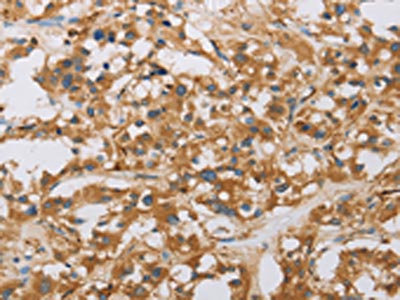

The image on the left is immunohistochemistry of paraffin-embedded Human thyroid cancer tissue using CSB-PA098715(RAD54L2 Antibody) at dilution 1/40, on the right is treated with fusion protein. (Original magnification: ×200)